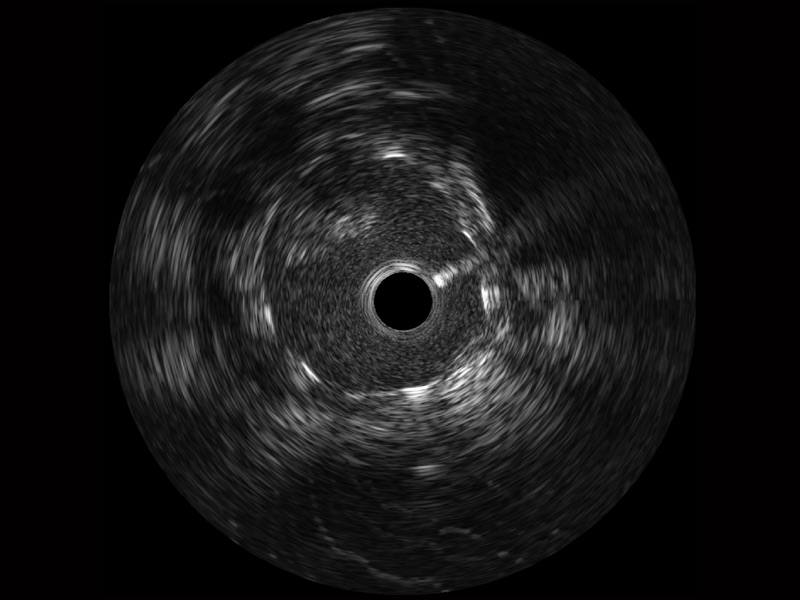

• 哈哈体育官网宽频IVUS图像

• 传统IVUS图像

对比传统IVUS导管成像,哈哈体育官网宽频IVUS图像的近场支架梁显影更细腻,远场中膜外血管仍清晰可辨,兼顾远中近,兼顾分辨力与穿透深度